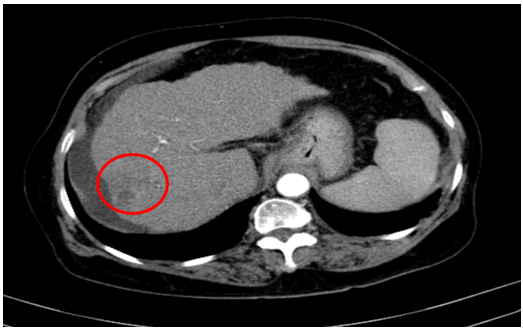

Tháng 8 năm 2024

Chụp cắt lớp vi tính ổ bụng

Gan: biến đổi hình thái, bờ không đều. Nhu mô gan phải có khối giảm tỉ trọng kích thước 26x25mm, ranh giới không rõ, co kéo bao gan lân cận,trong có hình ảnh tăng tỉ trọng của vật liệu nút mạch, sau tiêm có phần ngấm thuốc ngấm thuốc.

Dịch quanh gan 8mm., dịch tự do ổ bụng

=> Hình ảnh u gan phải sau điều trị hiện còn phần ngấm thuốc (Vòng tròn đỏ) /Xơ gan